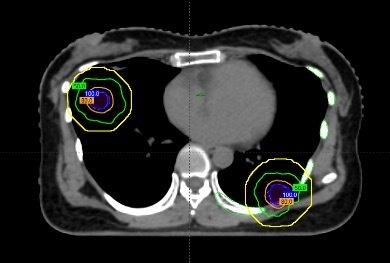

这三个病灶有几个共同特点:一是体积很小,直径均不到1厘米;二是位置分散,分别位于不同肺叶;三是其中一个紧贴肋骨,几乎没有“安全距离”。

在治疗前,团队通过四维CT对三个病灶进行精准定位,尤其是紧贴肋骨的那个病灶,连与肋骨之间极其细微的间隙都被清晰标注出来。

随后进入最核心的剂量设计环节。医生与李忠伟、雷大明物理师反复推演射线路径和强度分布,把高剂量区域严格控制在肿瘤范围内,同时让剂量在极短距离内迅速下降。可以理解为,在体内完成了一次“毫米级雕刻”:肿瘤被精准覆盖,而近在咫尺的肋骨却被保护在安全范围内。